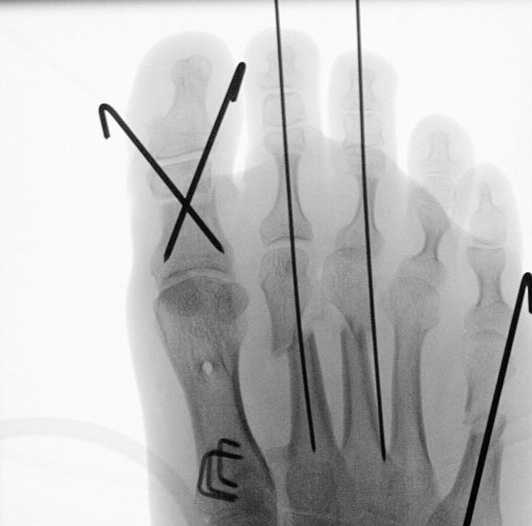

=> Risikoabwägung der radiologisch leicht erhöhten Strahlenbelastung intraoperativ

In der minimalinvasiven Fußchirurgie ist es unabdingbar, die Fräse in ihrer Position zum Knochen radiologisch zu kontrollieren, damit vulnerable Wachstumsfugen oder angrenzende Gelenke nicht verletzt werden. Zu diesem Zweck werden mit einem Bildwandler während der Operation die genaue Position der Fräse und der Osteotomieverlauf überprüft, was die Strahlenbelastung im Vergleich zu offenen Verfahren erhöht. Diese Strahlenbelastung hat potenziell einen schädigenden Einfluss auf den noch blutbildenden Knochen von Heranwachsenden. Gesicherte Landmarken am Fuß können die notwendige Zahl der Röntgenbilder und damit die Strahlung minimieren. Ist es erforderlich, mehrere Knochen zu osteotomieren, wie zum Beispiel im Bereich der Kleinzehen, werden anhand der Landmarken kleine Injektionsnadeln auf Höhe der geplanten Osteotomien vorgelegt und radiologisch im Bildwandler (BV) dokumentiert (Abb. 11). Ein solches Bild schafft eine gute Orientierung, sodass auf radiologische Kontrollen intraoperativ weitestgehend verzichtet werden kann.

Abb. 11: Lokalisation mehrerer Stichinzisionen mit einem Röntgenbild.